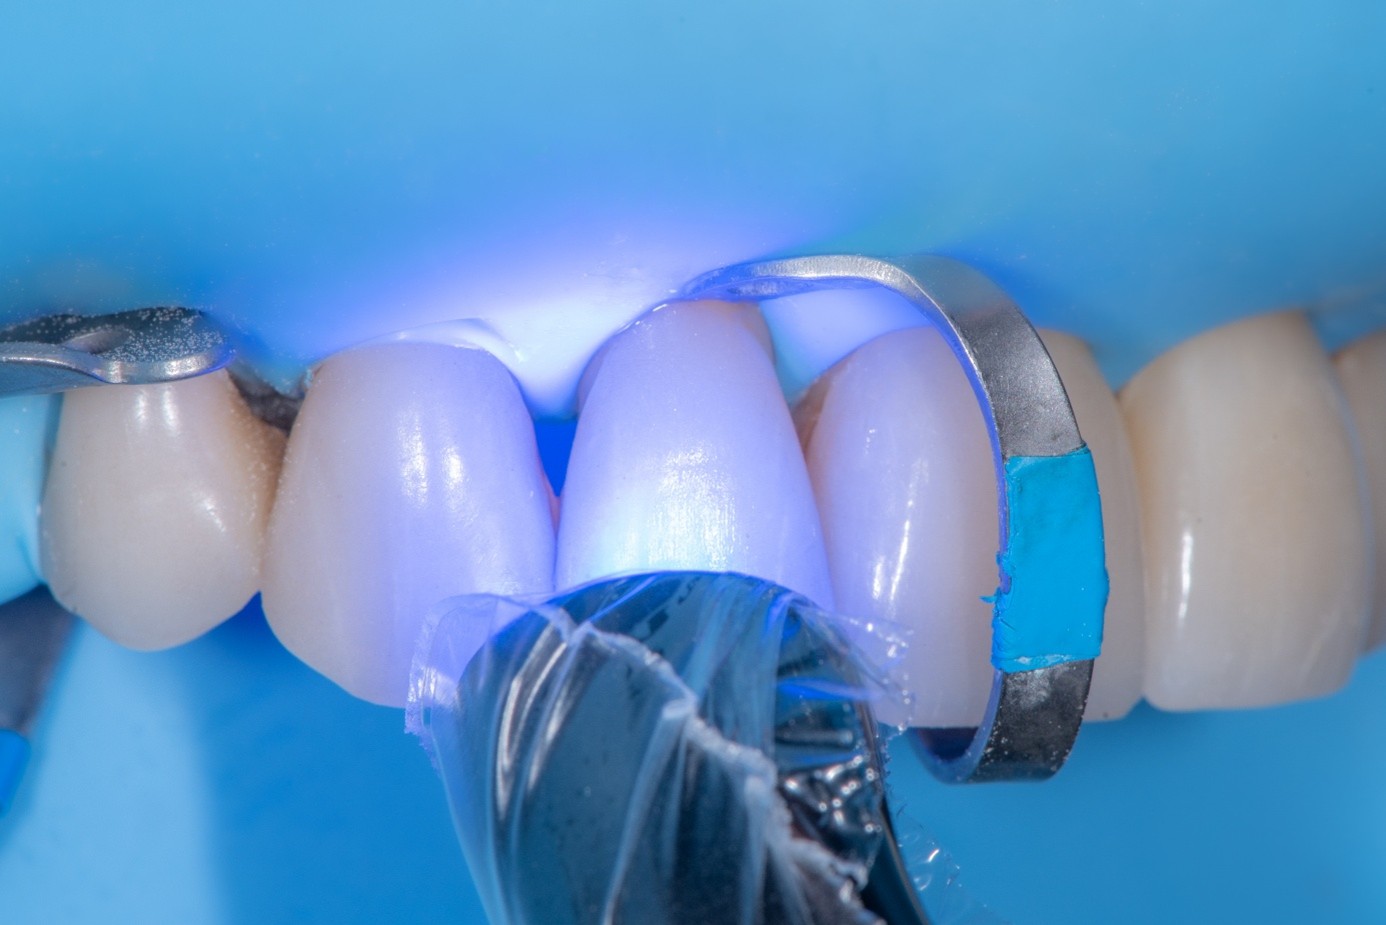

(21.) Intraoral view after rubber dam isolation, showing prepared surfaces: both sandblasted and etched, with silanization applied only to the composite surface, ready for reattachment.

Figure 21

(22.) Intraoral view after rubber dam isolation, showing prepared surfaces: both sandblasted and etched, with silanization applied only to the composite surface, ready for reattachment.

Figure 22

(23.) Intraoral view after rubber dam isolation, showing prepared surfaces: both sandblasted and etched, with silanization applied only to the composite surface, ready for reattachment.

Figure 23

(24.) Intraoral view after rubber dam isolation, showing prepared surfaces: both sandblasted and etched, with silanization applied only to the composite surface, ready for reattachment.

Figure 24

After achieving rubber dam isolation, the fractured composite segment was first air-abraded with aluminum oxide particles to clean and roughen the surface. It was then etched with phosphoric acid for 60 seconds, rinsed, dried, and treated with silane to enhance chemical adhesion (Figure 18 through Figure 20).8,9

The tooth surface was similarly air-abraded to remove biofilm and aged resin remnants, then selectively etched with phosphoric acid. Silane was applied intraorally to the exposed composite surface to promote bonding between the old and new composite layers.10 Following this, a universal bonding agent was applied to both the tooth surface and the fractured composite segment (Figure 21 through Figure 24).